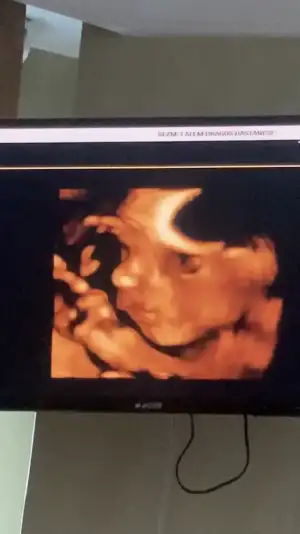

artık 15 de bir gidicem artık, benim uzunluktan ziyade kafa pozisyonu çok çok aşağıda. O yüzden yüzünü görmek imkansız gibi bir şeymiş artık